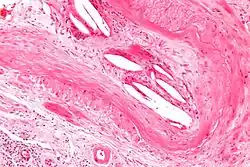

Micrograph showing a cholesterol embolus in a medium sized artery of the kidney. Kidney biopsy. H&E stain.

The microscopic examination of tissue (histology) gives the definitive diagnosis. The diagnostic histopathologic finding is intravascular cholesterol crystals, which are seen as cholesterol clefts in routinely processed tissue (embedded in paraffin wax).[7] The cholesterol crystals may be associated with macrophages, including giant cells, and eosinophils.

The sensitivity of small core biopsies is modest, due to sampling error, as the process is often patchy. Affected organs show the characteristic histologic changes in 50-75% of the clinically diagnosed cases.[3][5] Non-specific tissue findings suggestive of a cholesterol embolization include ischemic changes, necrosis and unstable-appearing complex atherosclerotic plaques (that are cholesterol-laden and have a thin fibrous cap). While biopsy findings may not be diagnostic, they have significant value, as they help exclude alternate diagnoses, e.g. vasculitis, that often cannot be made confidently based on clinical criteria.